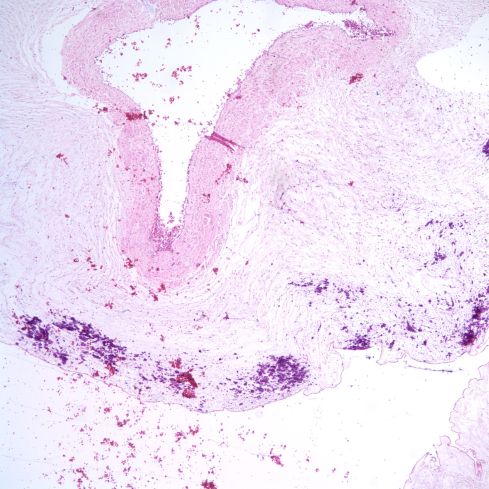

Similarly, the occurences of SNF with HSV virus appears to reflect deeper invasion into Wharton’s jelly (Fig 10)

Fig 10a) The umbilical cord shows minimal findings of SNF.

Fig 10b) Just beneath the surface there is a chronic inflammatory infiltration and necrotic cells.

Fig 10c) In some areas there appear to be plasma cells.

Fig 10d) An anti-HSV immuno-stain demonstrates that the cells in Wharton’s Jelly had become infected with HSV.